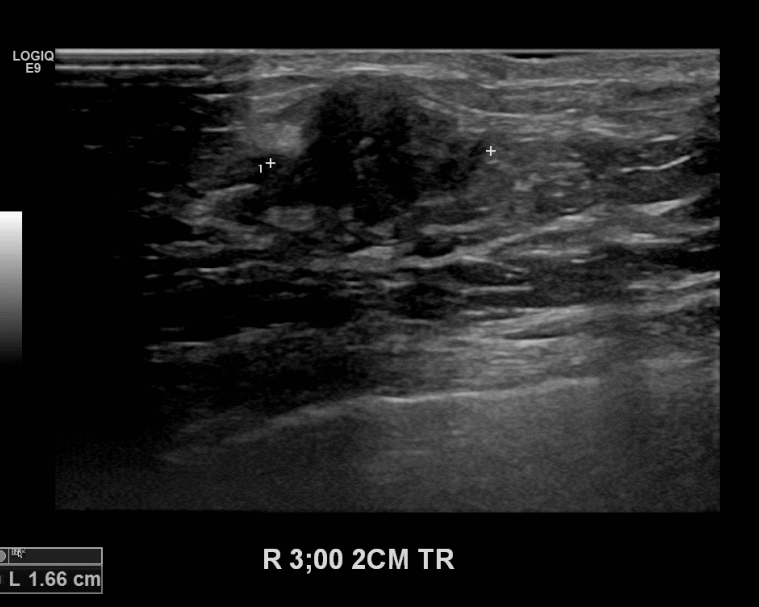

상기환자 우측유방의 만져지는 멍울있어 내원하신 50대 여성으로 유방초음파검사 이후

의심스러운 혹 조직검사시행후 유방암 진단되었습니다